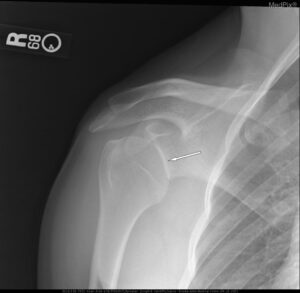

Joint dislocation occurs when a joint separates or dislocates abnormally disrupting the normal alignment of a joint. Joints may also sublux and this occurs when the joint begins to dislocate but has not yet lost contact on two sides of the joint. Dislocations occur commonly in the shoulder and finger joints. Physical Therapy can help identify tight and weakened muscles around the joint and design exercises to help promote balance and teach joint protection strategies and proper posture.